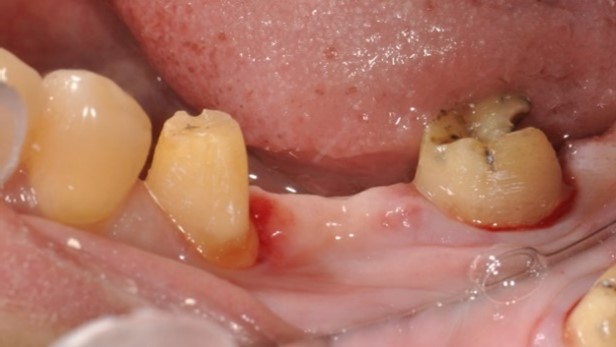

將牙齒拔出後,在口外做根管治療、並且切除牙根末端神經較複雜處。

醫師在口外對牙齒完成治療後,再將牙齒植入同一位置

治療中:牙齒在口外治療完種回去,並用鐵線固定,等待傷口復原.

治療中:將牙齒修型、將鐵線拆除